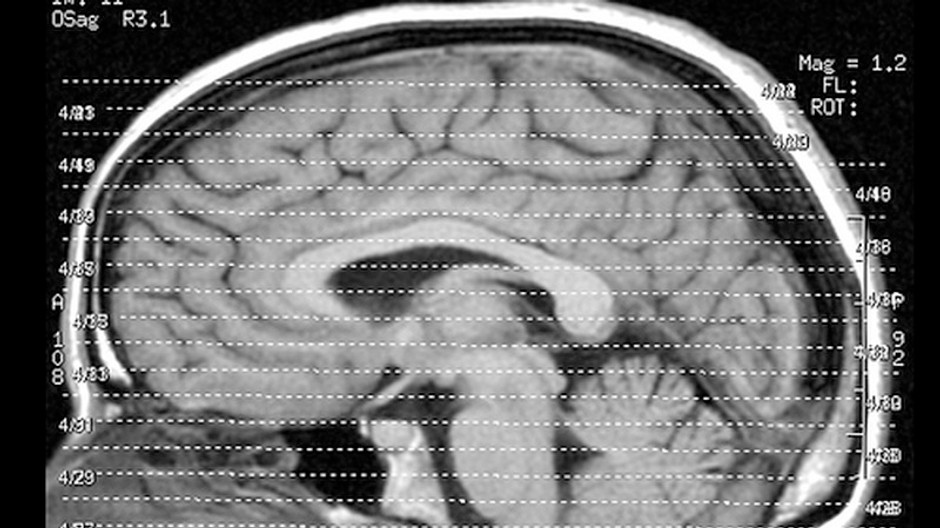

Zdroj: Liz Henry/ilustračné

BRATISLAVA / Mŕtvica je druhou najčastejšou príčinou úmrtí na celom svete. Netýka sa však len starších ľudí, postihuje čoraz mladších. Pritom sa mŕtvici dá až v sedemdesiatich percentách prípadov predísť.